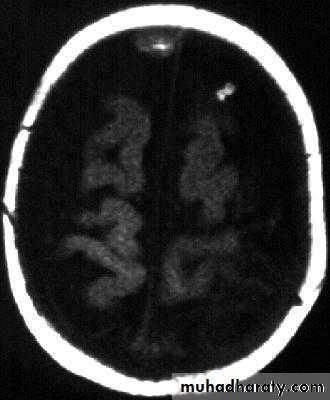

Bacterial Meningitis with cerebral oedema

Bacterial Meningitis with suppuration